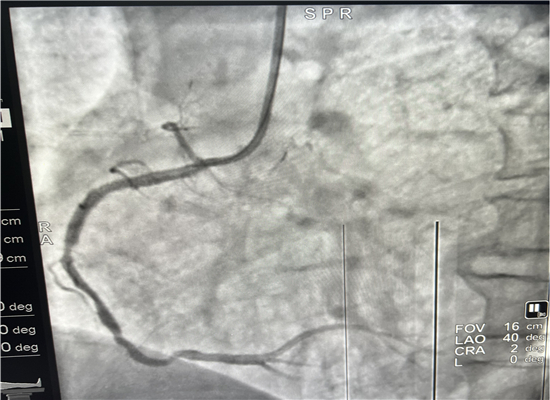

介入手术前

介入手术后